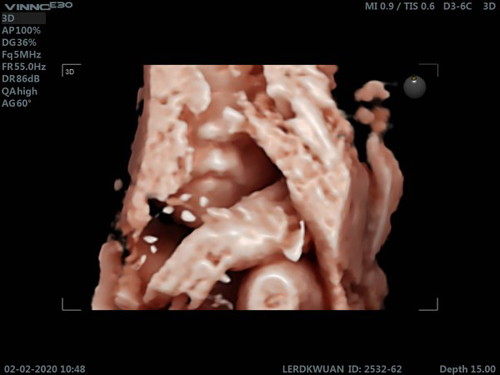

หนุ่มน้อยขี้อาย

หมอพยายามจะให้แม่เห็นหน้าชัดๆ แต่ตัวเล็กเอาแต่มุดหนีให้ดูแค่นี้จริงๆ ?

ปากชัดมาก อย่างอื่นไม่เห็นเลย 😂😂😂